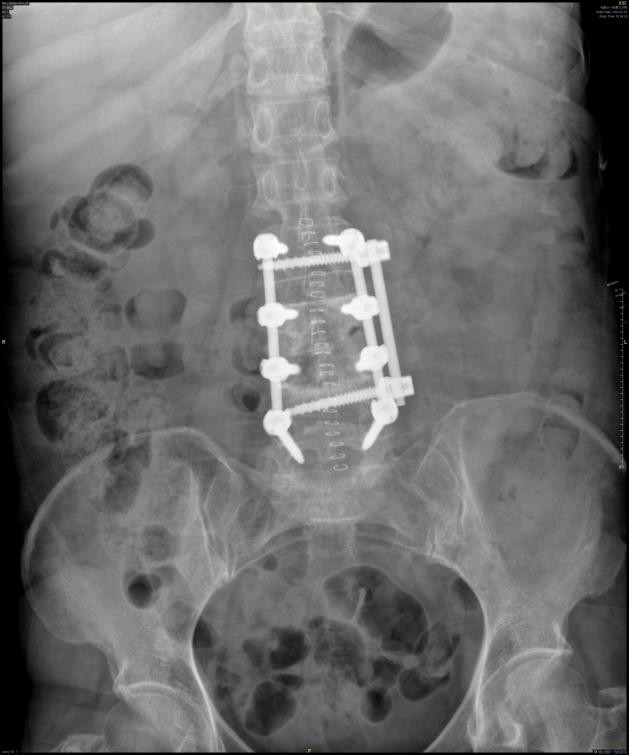

术后复查X线显示腰椎前柱重建效果满意